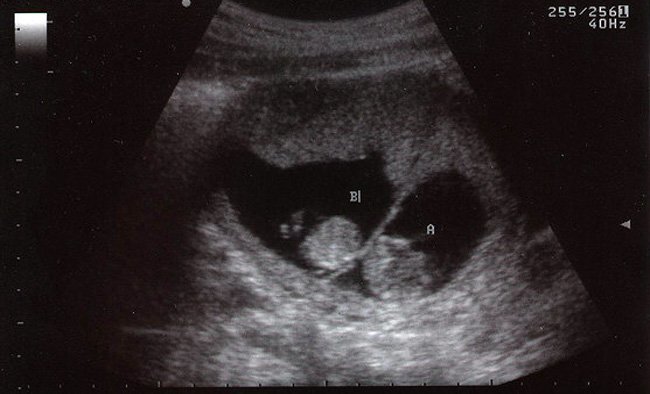

El cuerpo de la mujer ha sido concebido para albergar gestaciones de un sólo embrión. Por lo tanto, un embarazo múltiple está asociado a un mayor riesgo de experimentar ciertas complicaciones durante la gestación.

Esto no significa que necesariamente ocurran complicaciones en el embarazo de gemelos, ya que la mayoría de estos niños nacen perfectamente sanos, pero si estás esperando dos o más bebés conviene estar al tanto de los posibles riesgos.

Las complicaciones más comunes en el embarazo de gemelos son: